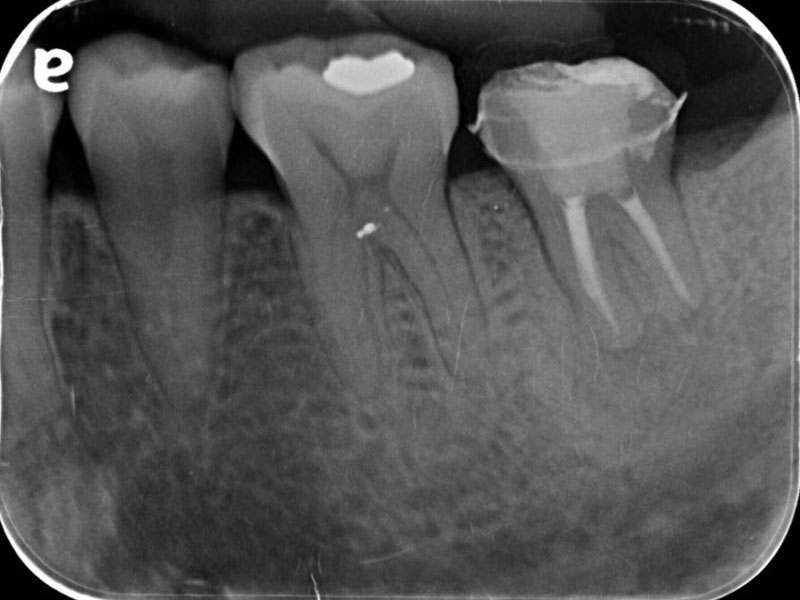

圖例為案例分享:

分離器械移除B-1

分離器械移除B-2